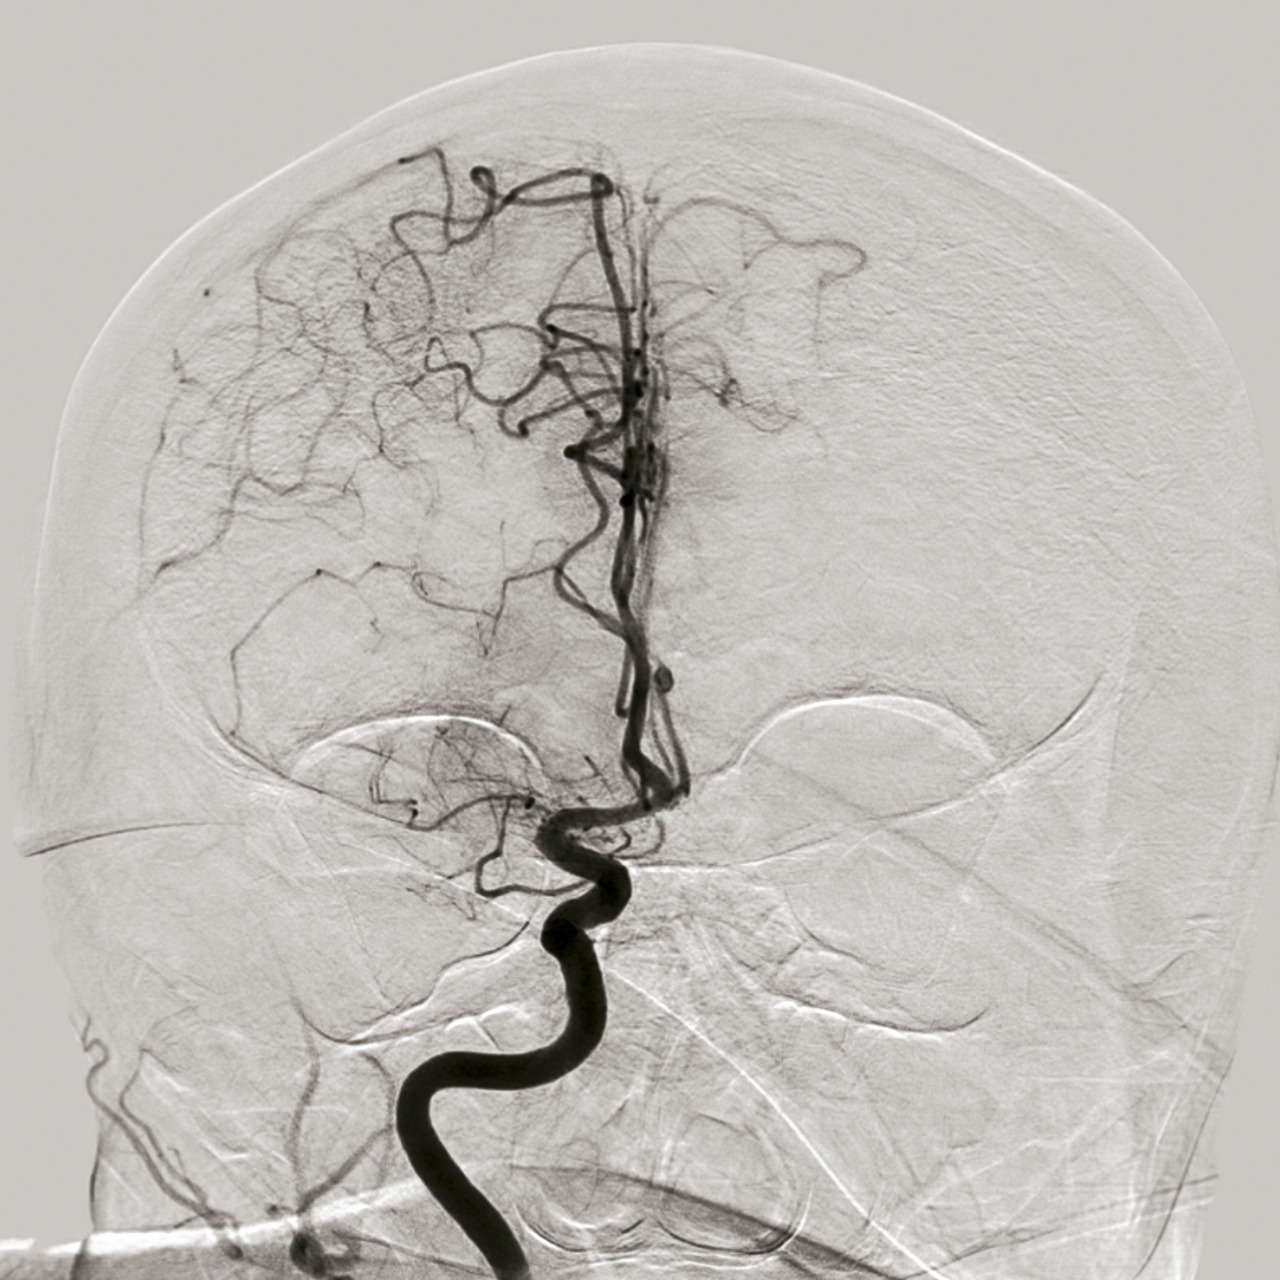

En 2015, cinq essais thérapeutiques ont prouvé l’efficacité de la thrombectomie mécanique en association à la thrombolyse IV dans le traitement des AVC ischémiques avec occlusion des artères de gros calibre de la circulation antérieure (artères carotide interne et moyenne proximale, fig. 1 à 4).6 La thrombectomie mécanique peut être réalisée avec des stents retriever (stents déployés mais non implantés) et/ou des dispositifs d’aspiration. L’effet de la thrombectomie mécanique est majeur, avec un nombre de patients à traiter de 2,6 pour éviter la dépendance,6 alors qu’il est estimé que pour 1 000 patients traités par thrombolyse IV, 41 éviteront la mort ou la dépendance.7 La thrombolyse IV est par ailleurs limitée par une augmentation du taux d’hémorragie intracrânienne symptomatique responsable d’une surmortalité durant les 7 premiers jours ; de faibles taux de recanalisation (au mieux 30 %, alors que la thrombectomie mécanique permet des taux de 80 à 90 %) en cas d’occlusion proximale intracrânienne ; sans oublier de nombreuses contre-indications (traitements anticoagulants, chirurgie récente…).